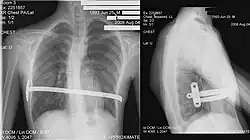

Bei der sogenannten „Nuss-OP“, die erstmals 1998 von Donald Nuss beschrieben wurde,[17][18] wird durch zwei kleine Schnitte an den Seiten unter den Achseln ein individuell ausgemessener und vorgebogener Metallbügel unter das Brustbein geschoben. Dieser drückt das eingesunkene Brustbein und die betroffenen Rippen nach außen. Der Bügel wird seitlich fixiert. In manchen Fällen werden auch zwei oder drei Bügel eingebracht. Das Ergebnis ist sofort sichtbar.

Meist bleibt der Bügel für zwei bis drei Jahre im Körper und wird dann operativ entfernt; bei älteren Patienten ist eine längere Zeit erforderlich. Seit 1999 wird die Methode auch in Deutschland durchgeführt. Aufgrund der kleinen Narben ziehen viele Patienten diese Methode der offenen Methode nach Mark Michael Ravitch vor.[19]